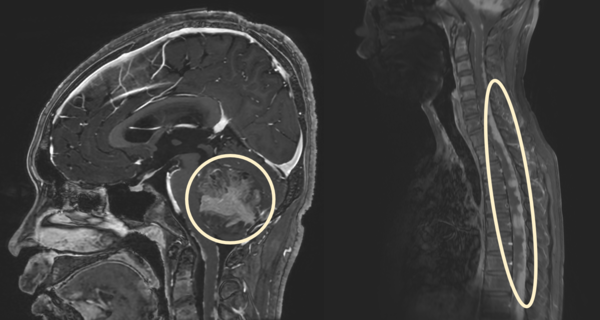

수모세포종은 악성 소아 뇌종양 중 가장 흔한 유형으로, 주로 소뇌에 발생하며 뇌척수액을 따라 전이가 잘 되는 종양이다. 환자 중 80% 이상은 뇌척수액이 비정상적으로 축적되는 수두증을 동반한다. 수술과 방사선·항암치료의 발전으로 치료 성적이 향상되고 있지만, 진단 시 10명 중 3명은 연수막 전이가 있으며 이런 고위험 환자들은 여전히 예후가 나쁘다.

이를 식별하기 위해 치료 중 척수 MRI와 뇌척수액 검사가 이뤄지지만, 이 같은 기존 검사 방법은 민감도가 떨어지기 때문에 임상 현장에서 더욱 정확한 연수막 전이 검사 방법에 대한 필요성이 높았고, 이를 위해 진단 바이오마커 발굴이 필요한 상황이었다.